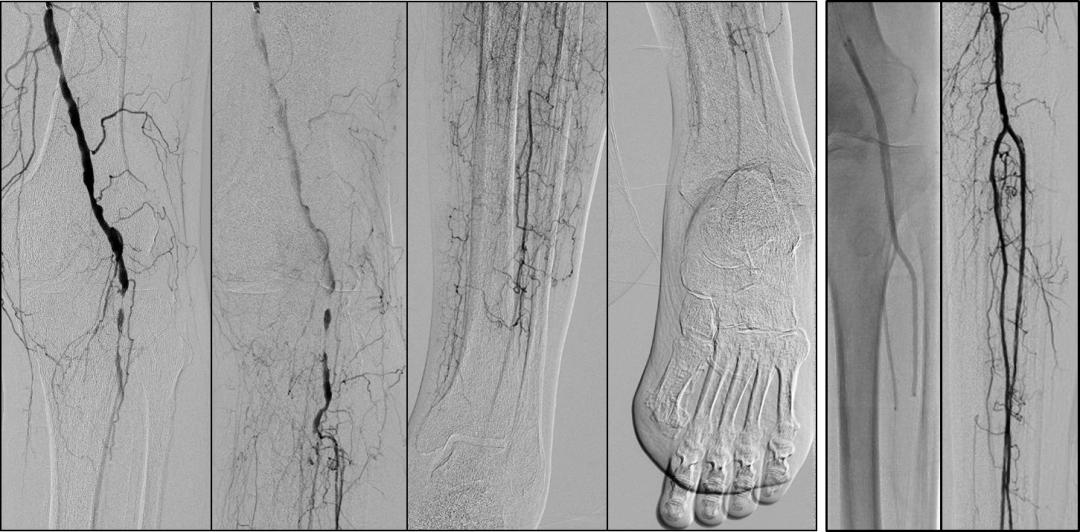

针对BTK病变,可采用多种腔内技术:

顺行技术

Knuckle/ADR(Antegrade Dissection and Re-entry)

AFR(Antegrade Fenestration and Re-entry)

BAM(Balloon-Assisted Microdissection)

BASE(Balloon-Assisted Subintimal Entry)

Stick-and-go

Stick-and-swap

Scratch-and-go

在操作中需遵循两大核心原则:

ALARA原则:在保证疗效的前提下,尽可能降低辐射剂量和造影剂用量。

区域化操作策略:

平直区域:可快速通过(真腔或内膜下);

关键区域(如CTO开口、出口、BTA区域):必须谨慎操作,避免穿孔等并发症。